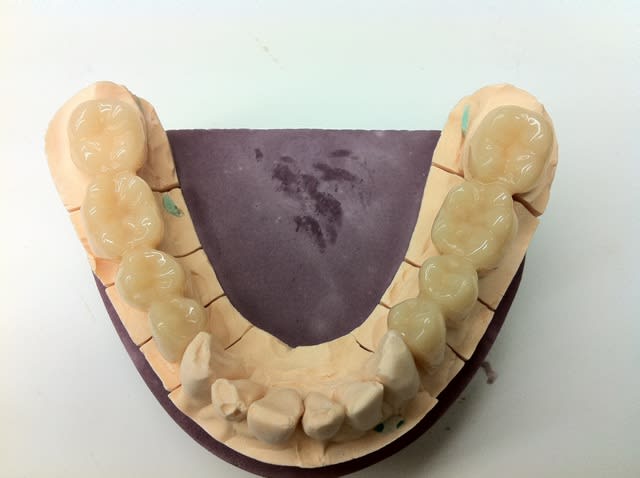

Voici les photos de la CAO, le soft m'a proposé un bridge décalé et en sous occlusion quoique bien fouillé comme expliqué précédemment,en le corrigeant j'ai perdu en anatomie mais gagné en équilibre et en solidité, j'aurai sans doute pu retravailler d'avantage les formes.

les connexions apparaissent en rouge et ont été étendues au maximum.

Voici encore des photos concernant l'intrados et la sculpture des faces occlusales nécessaire pour ce bridge.